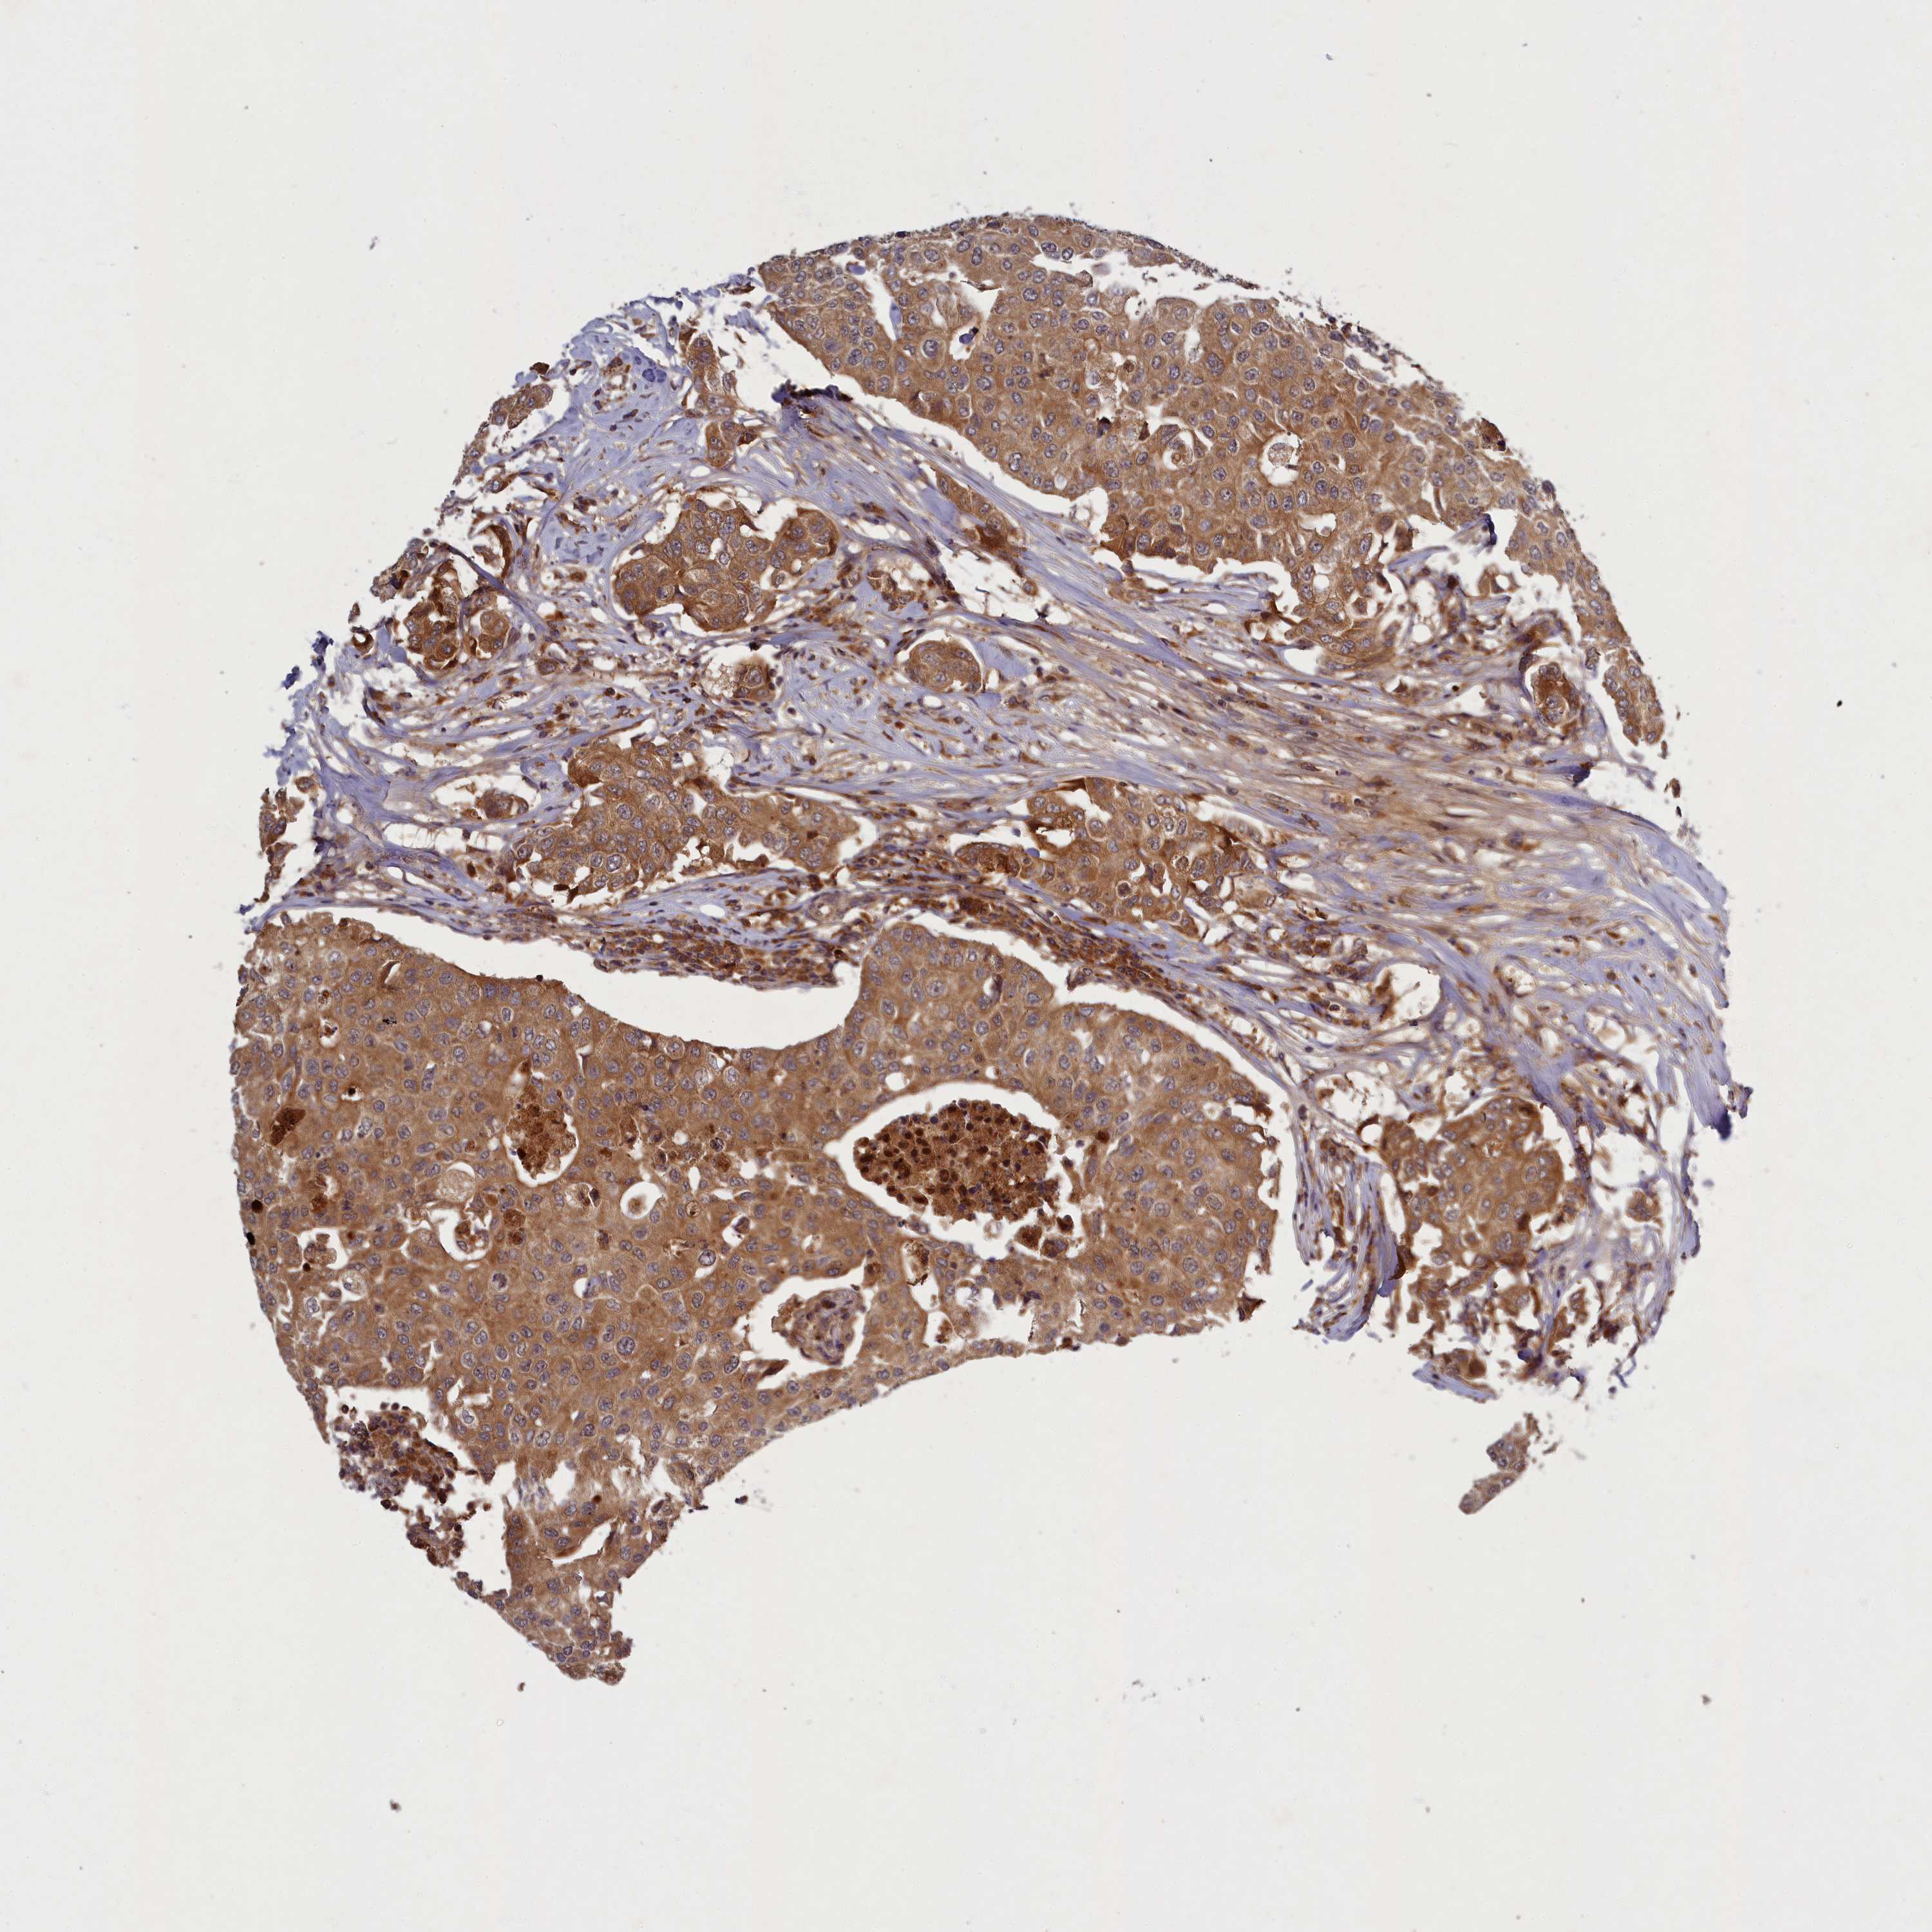

CANCER BREAST CANCER Show tissue menu

BRCA TCGA BRCA VALIDATION PROTEIN EXPRESSION

ANTIBODIES

AND

VALIDATION